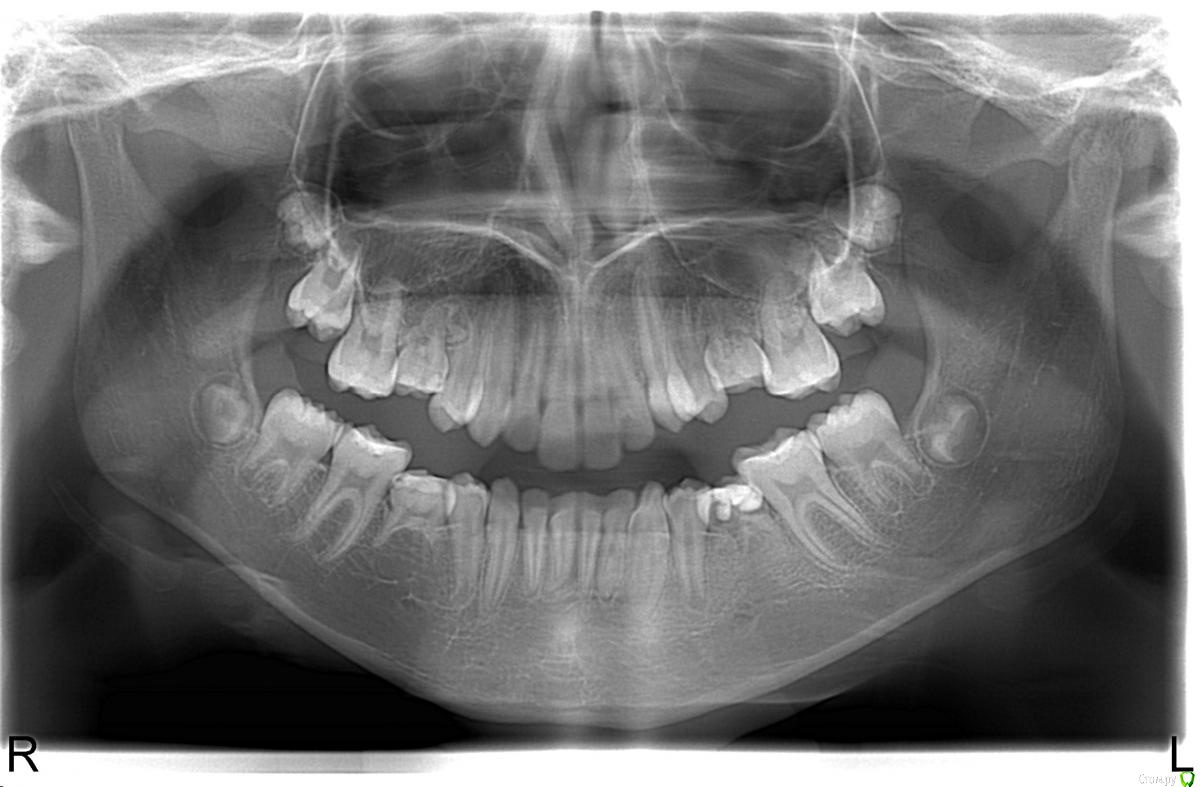

Cemenoff Опубликовано 6 февраля, 2017 Поделиться Опубликовано 6 февраля, 2017 Добрый день, Ребенок , девочка 10 лет, адекватная и мама и дочь. как поступить в данной ситуации?удалить молочные? (75 удален) или пусть держат место для роста челюсти?и получится ли в 13-14(может раньше?) лет подвинуть моляры медиально для закрытия промежутков.Как бы вы лечили ? Ссылка на комментарий

Cemenoff Опубликовано 6 февраля, 2017 Автор Поделиться Опубликовано 6 февраля, 2017 Спасибо. а в области 55 просто наблюдать? Может какой то активатор назначить для сохранения места в обл. 75, или распорку с кольцом на 26(может косметичку из нейлона) сделать, первый раз столкнулся Ссылка на комментарий

Yana guapa Опубликовано 6 февраля, 2017 Поделиться Опубликовано 6 февраля, 2017 (изменено) Спасибо. а в области 55 просто наблюдать? Может какой то активатор назначить для сохранения места в обл. 75, или распорку с кольцом на 26(может косметичку из нейлона) сделать, первый раз столкнулсяДоктор из ЧеМябинска , а Вы ортодонт? Вы сами хотите вести? для ясности картины)))) потому что если нет - то лучше пошлите к коллеге. Если сами планируете вести, то взвесьте все плюсы и минусы двух разных подходов в лечении (с удалением молочных пятерок и закрытием места или сохранением пятерок и последующим протезированием) Какой подход выберете Вы - зависит от многих факторов (и во что верите, и какой размер зубов, их положение, их гармоничность ... и тд, какими техника владеет врач... платежеспосбность пациента в целом и особенно в будущем(!) ) Мое личное мнение - сохранять пятерки и готовить под протезирование. По крайней мере не было у меня еще таких детей которым захотелось бы удалить и закрывать промежутки. если 7.5 удалили и остальные зубы будете сохранять, конечно берегите место тогда! каким способом выбирать вам (у съемного и несъемного свои + и -) заговорили про нейлон - а с чего вдруг нейлон в детской стоматологии? чем вам обычная пластмасса не нравится? и какая" косметичка"?? у детей мы сохраняем функцию (поэтому даже простонаречные термины не совсем уместны и не актуальны) Было бы хорошо, если бы кейс был выложен полностью, чтобы выбрать конструкцию (потому что если есть проблемы с прикусом, то можно сразу двух зайцев - и протезирование и лечение прикуса) Изменено 6 февраля, 2017 пользователем Yana guapa Ссылка на комментарий